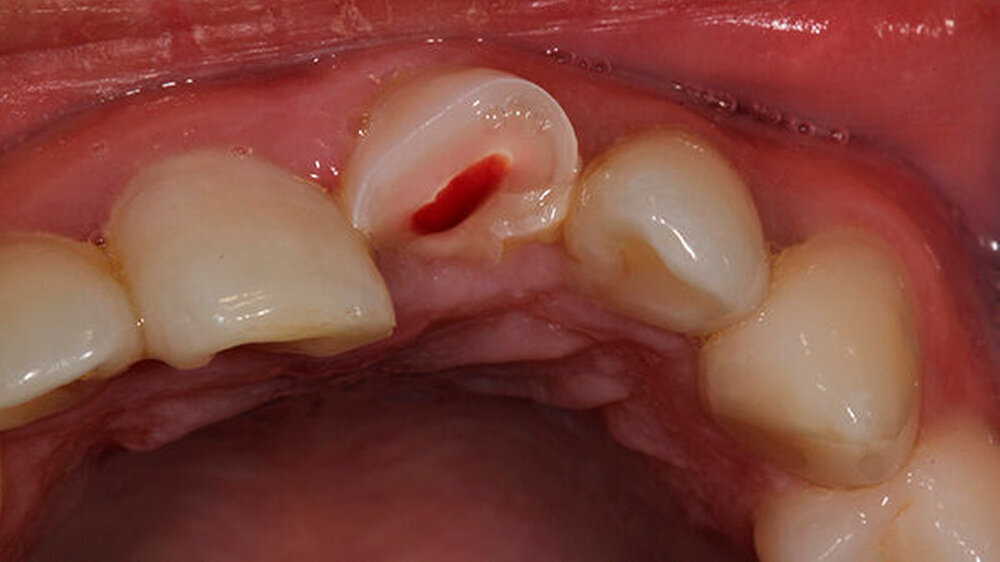

Oralchirurg Marcus Stoetzer arbeitete drei Monate lang im Feldlager der Bundeswehr in Mazar e Sharif - insgesamt behandelte er in Afghanistan 298 Soldaten. Die Bilder zeigen, aus welchem Grund sie zu ihm kamen.